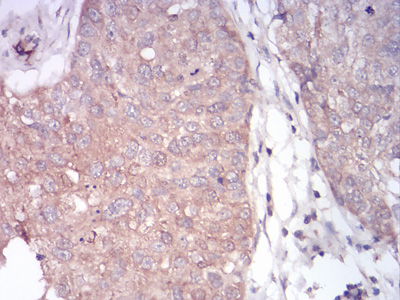

Immunohistochemical analysis of paraffin-embedded human cervical cancer tissues using anti-PLCG1 antibody. Counter stained with hematoxylin.

Immunohistochemical analysis of paraffin-embedded human bladder cancer tissues using anti-PLCG1 antibody. Counter stained with hematoxylin.